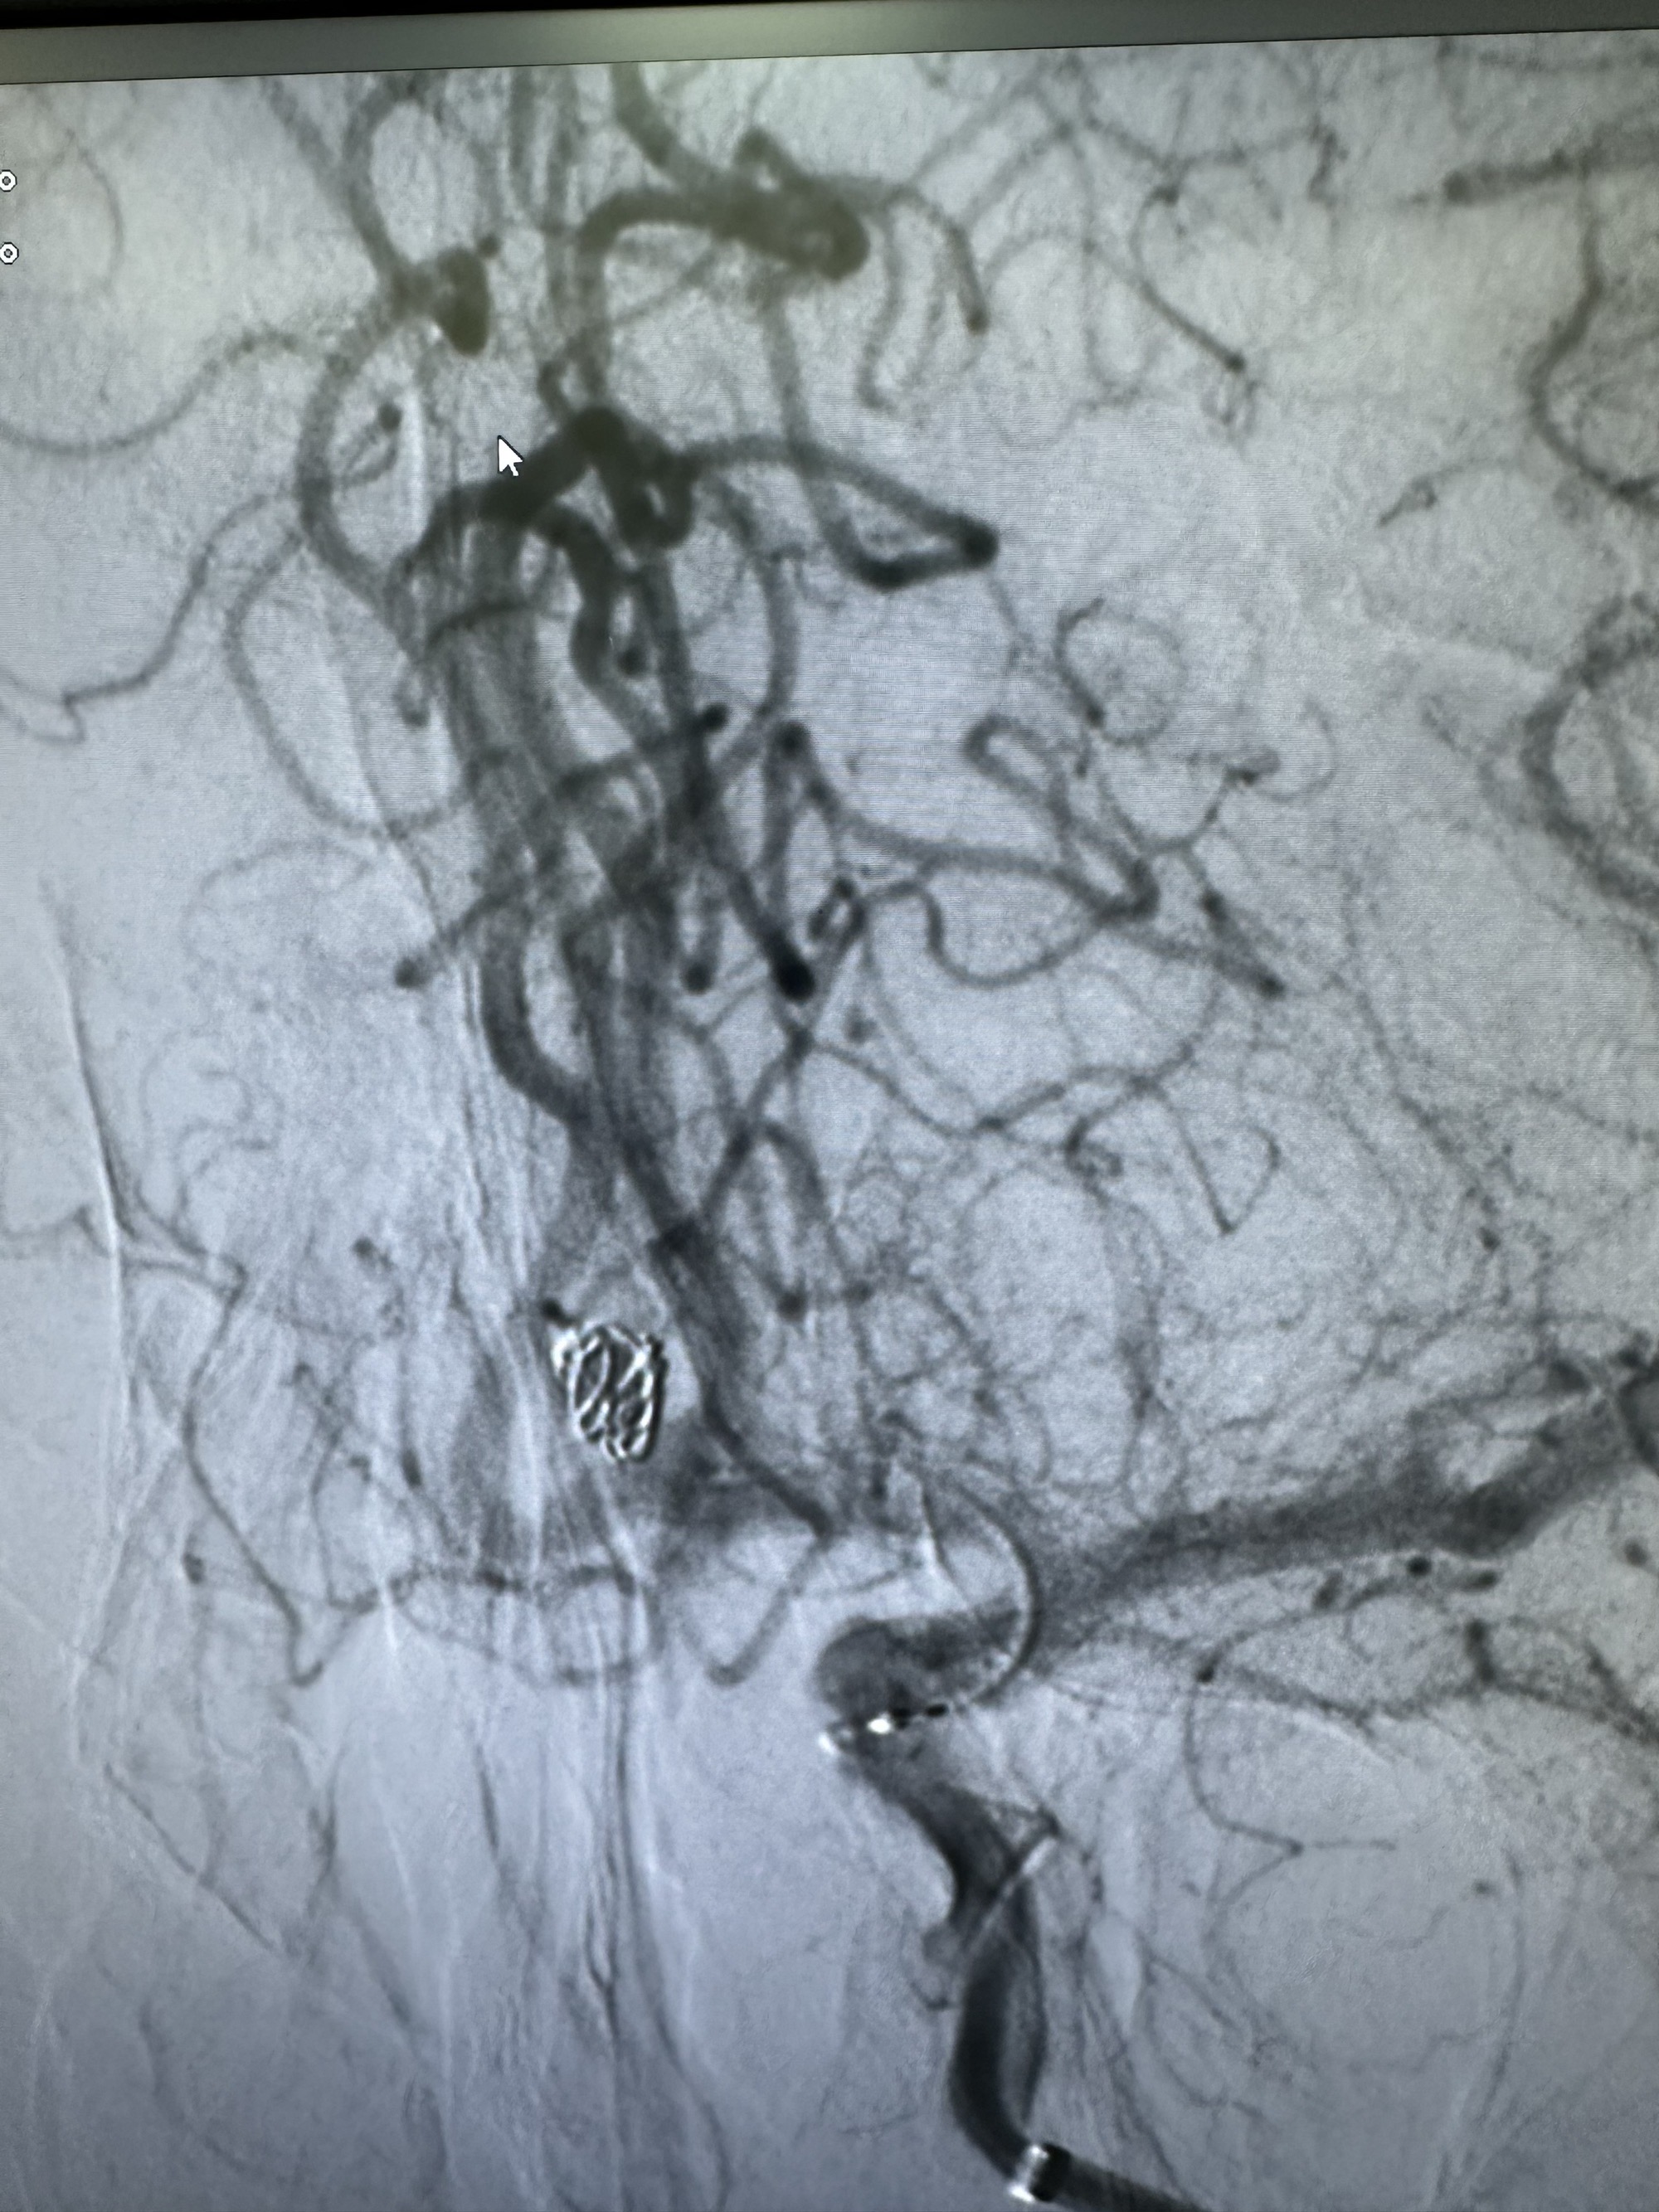

最后圈的形态

正位